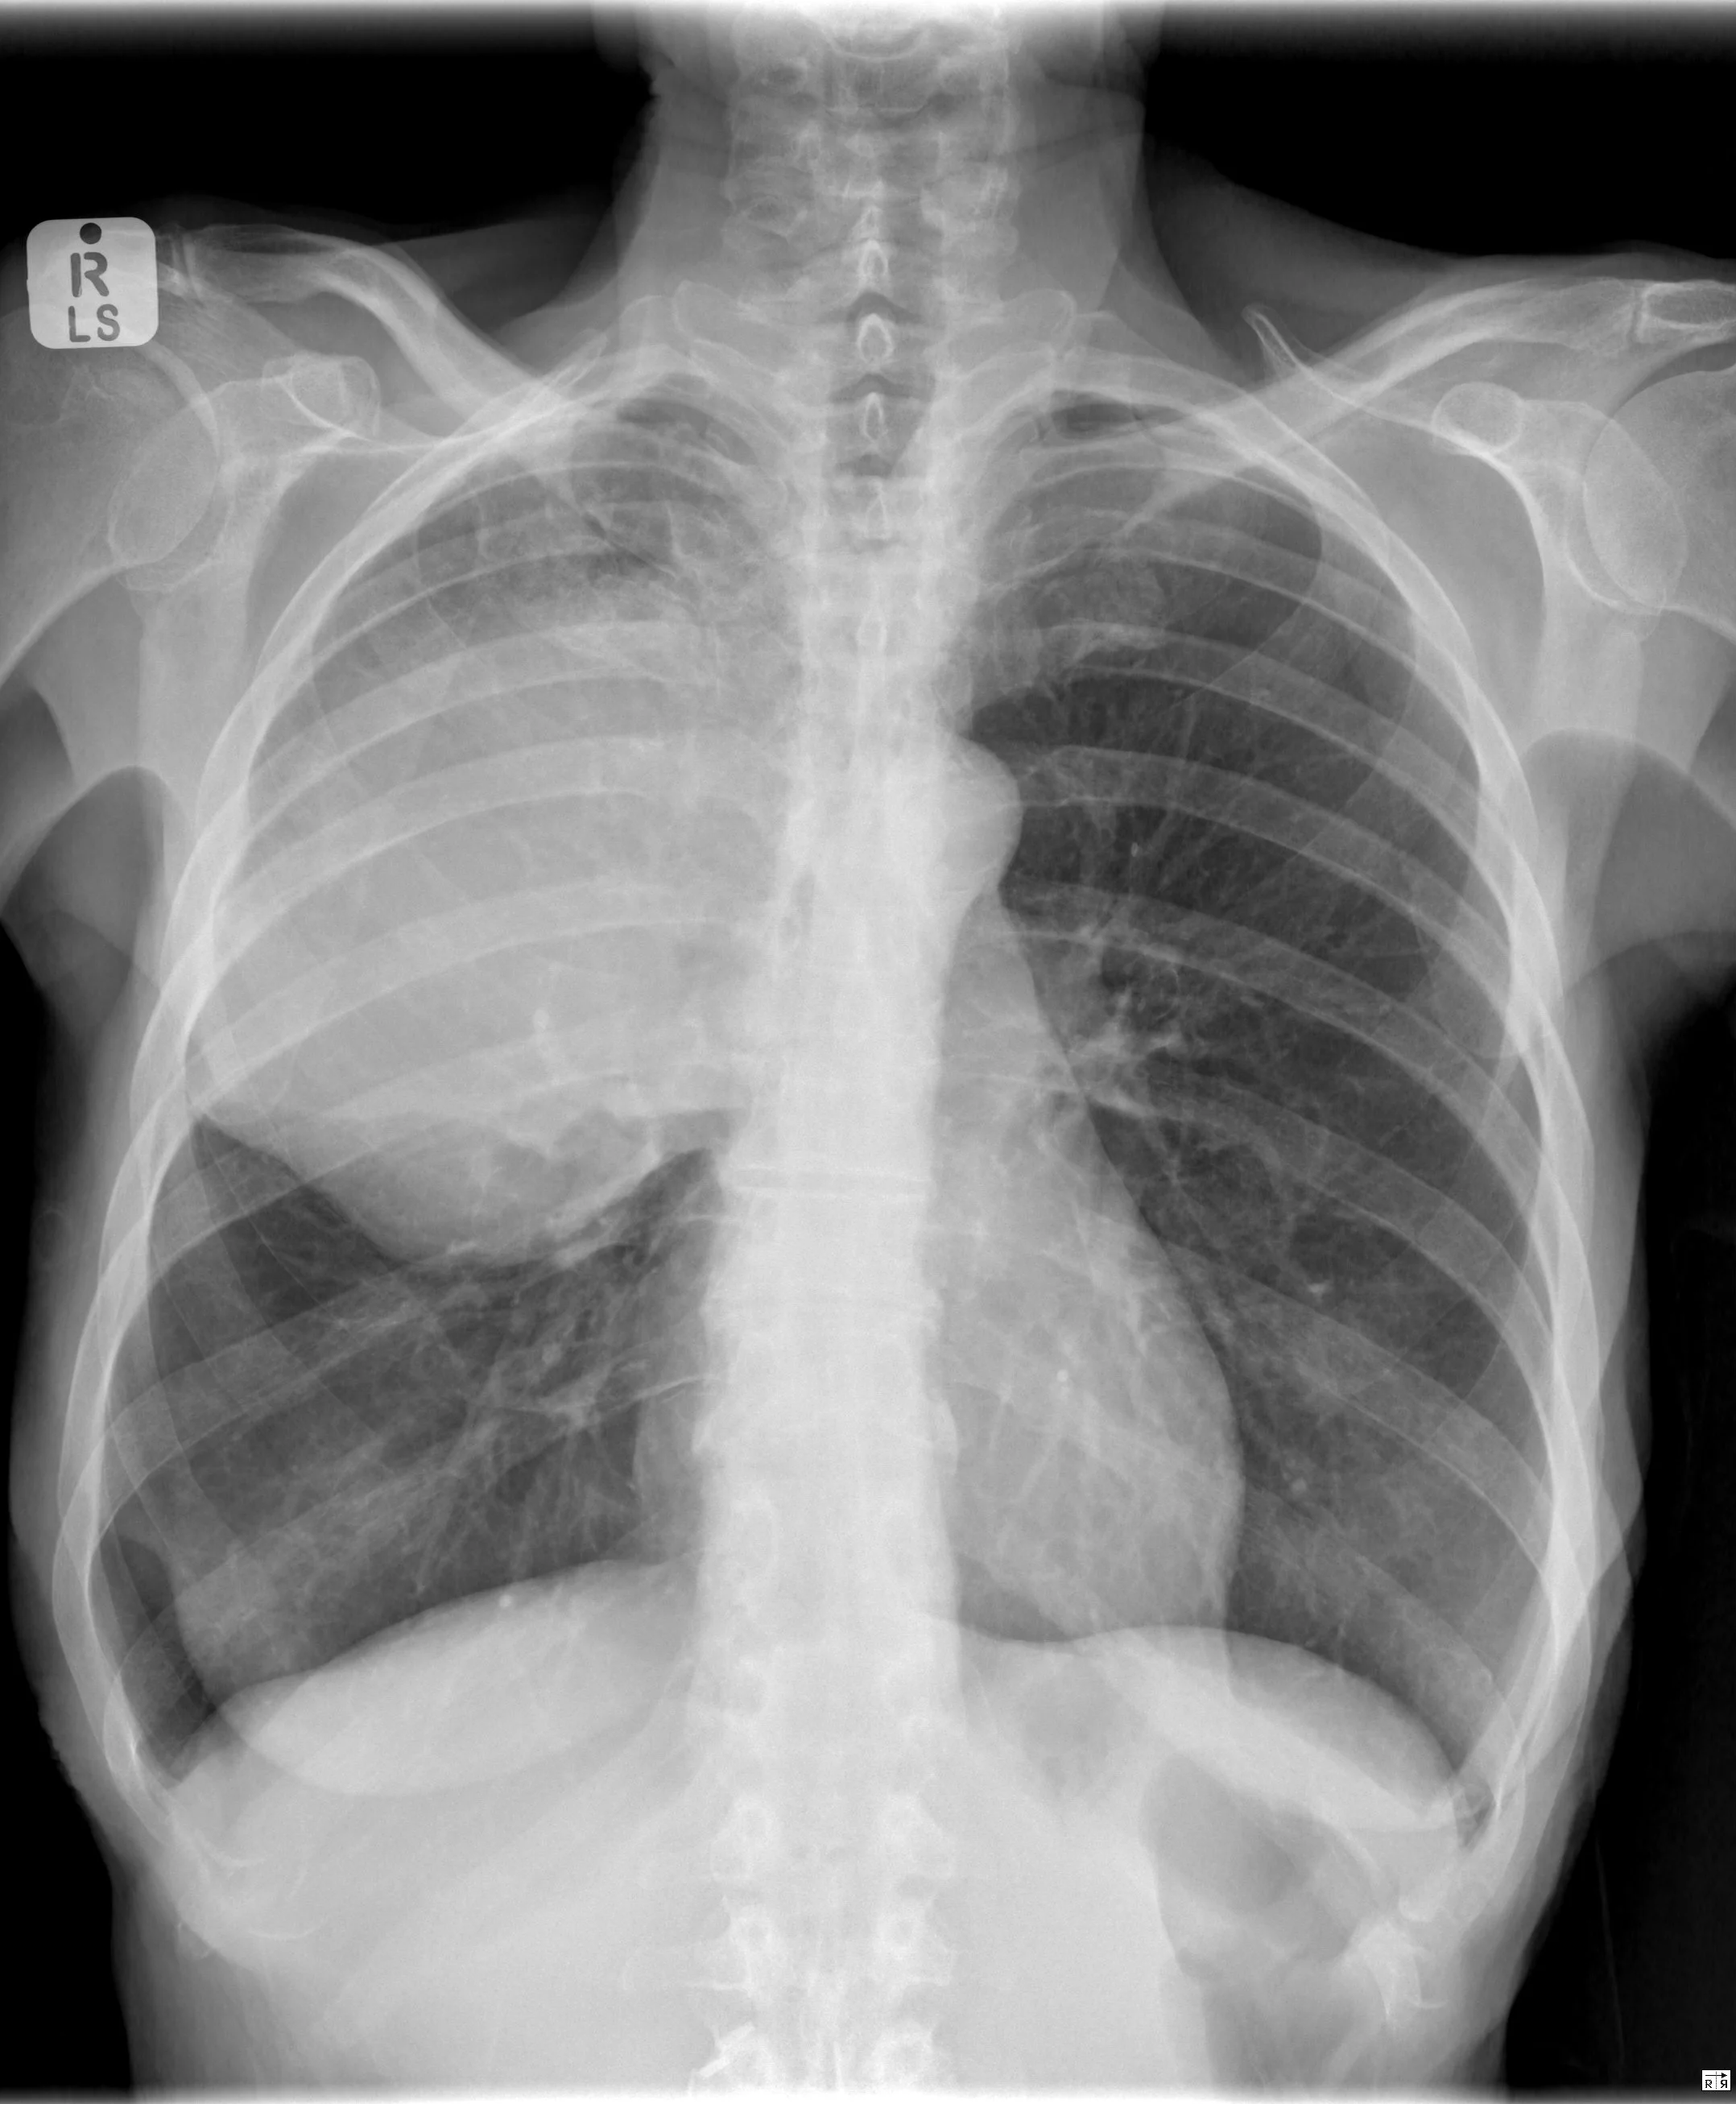

Bulging Fissure Sign

• Consolidation with expansion of the lung lobe such that the fissure boundary is displaced

• Caused by anything that occupies space and therefore exerts mass effect within the lung

• DDx:

• Pneumonia

• Classically seen in RUL secondary to Klebsiella pneumonia

• Strep pneumoniae, Staph aureus, Pseudomonas too

• TB

• Legionella

• Cancer (Adenocarcinoma of the lung)

• Pulmonary hemorrhage